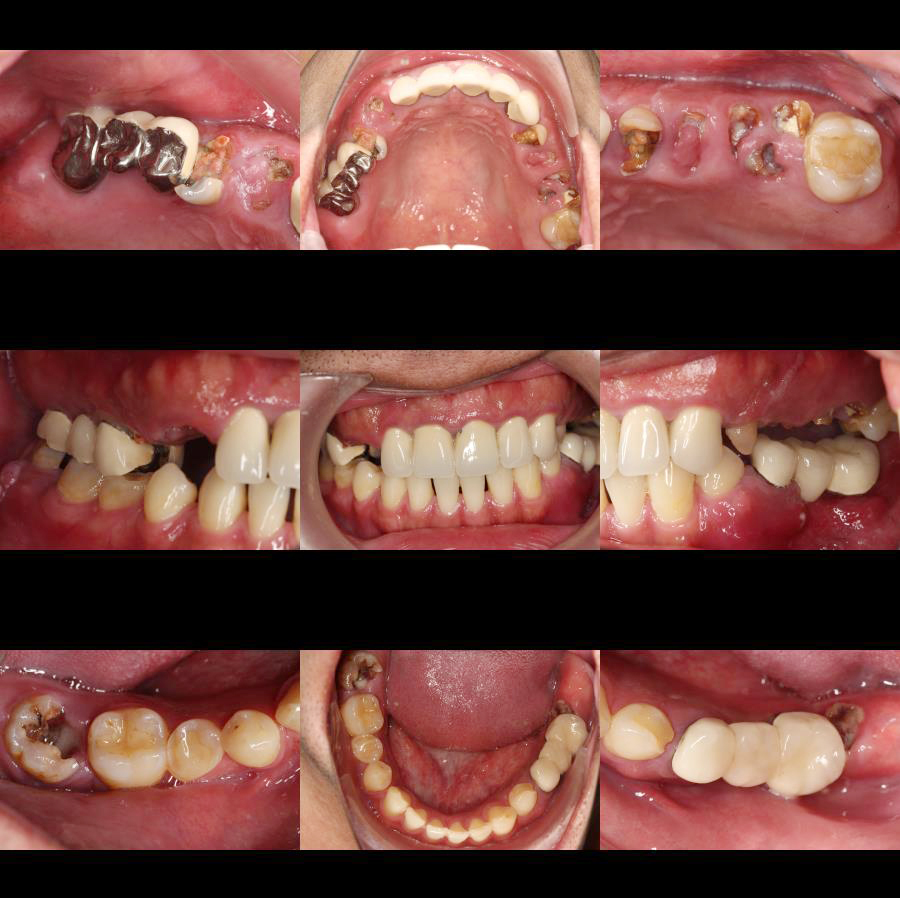

術前數位照片可以看出缺牙狀況,方便與患者說明口內條件

上顎:重建微笑曲線與支撐

上顎區域植入了多顆植體,特別是在前牙區與後牙區的配比。

前牙區: 恢復美觀與撕裂食物的功能。

後牙區: 提供強大的咀嚼支撐力。

下顎(Mandible):穩固的咬合基座

下顎骨質較硬,是主要的力學支撐點。